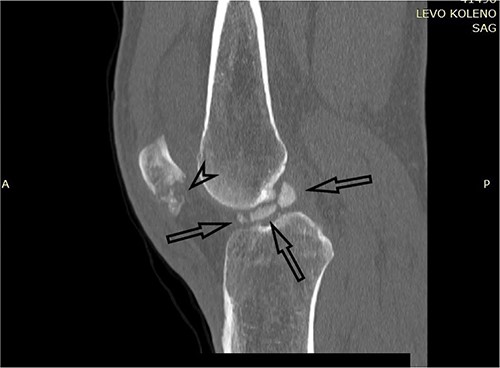

One month after index surgery, the patient was readmitted for the second intervention. In spinal anesthesia, the left knee was positioned for routine arthroscopy. During the procedure, it was concluded that the achievement of proper anatomical fragment repositioning and fixation is unobtainable. Therefore, conversion to arthrotomy followed via the lateral parapatellar approach. Fragments were fixed with two titanium headless compression screws (3.5 mm) (Fig. 4). The second postoperative period was uneventful. Early range of motion exercises started on postoperative Day 2. The patient was discharged on postoperative Day 4. The rehabilitation period lasted 4 weeks. Weight-bearing was allowed at Week 8 after surgery.

Postoperative plain X-ray of the left knee. (A) Anteroposterior view. (B) Lateral view.

Two years following the injury, the patient had a complete and painless range of motion in the left knee (Fig. 5).